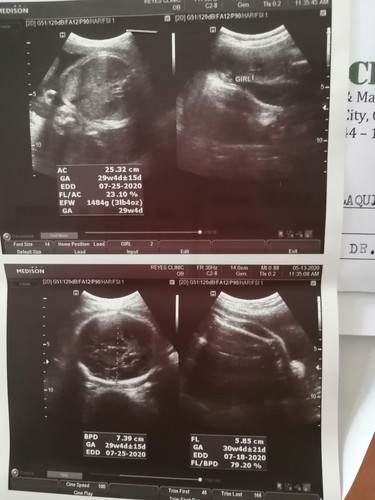

Ultrasound Result

Hello po. Ask ko lang po kung normal po ba ang result ng ultrasound ko. Yung size ni baby? Dipa po kase ako nakakabalik sa ob ko para ipakita ung result. Thanks po!

Nasan po un remarks ng ultrasound mo mommy?

Eto po mami